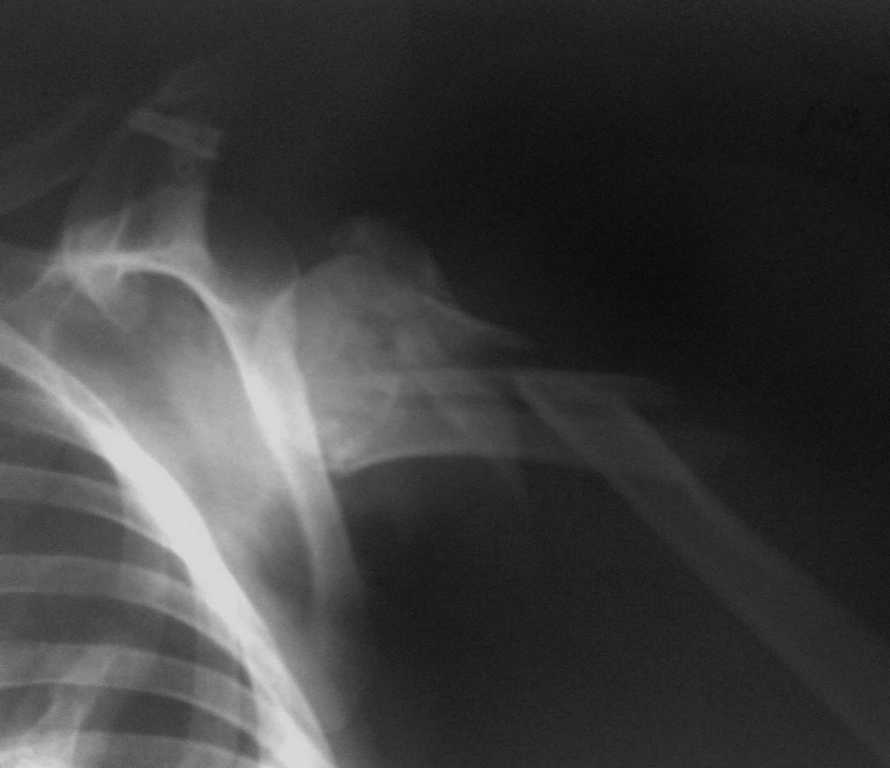

Переломо-вывих проксимального отдела плеча |

Пациентка, 51год, автодорожная политравма: закрытый двойной перелом левого бедра (оперирован - Биос),полный внутрисуставной перелом проксимального отдела левой голени (будет синтез LCP PLT на предстоящей неделе), переломо-вывих проксимального отдела правого плеча. Травма от 08.01.2009